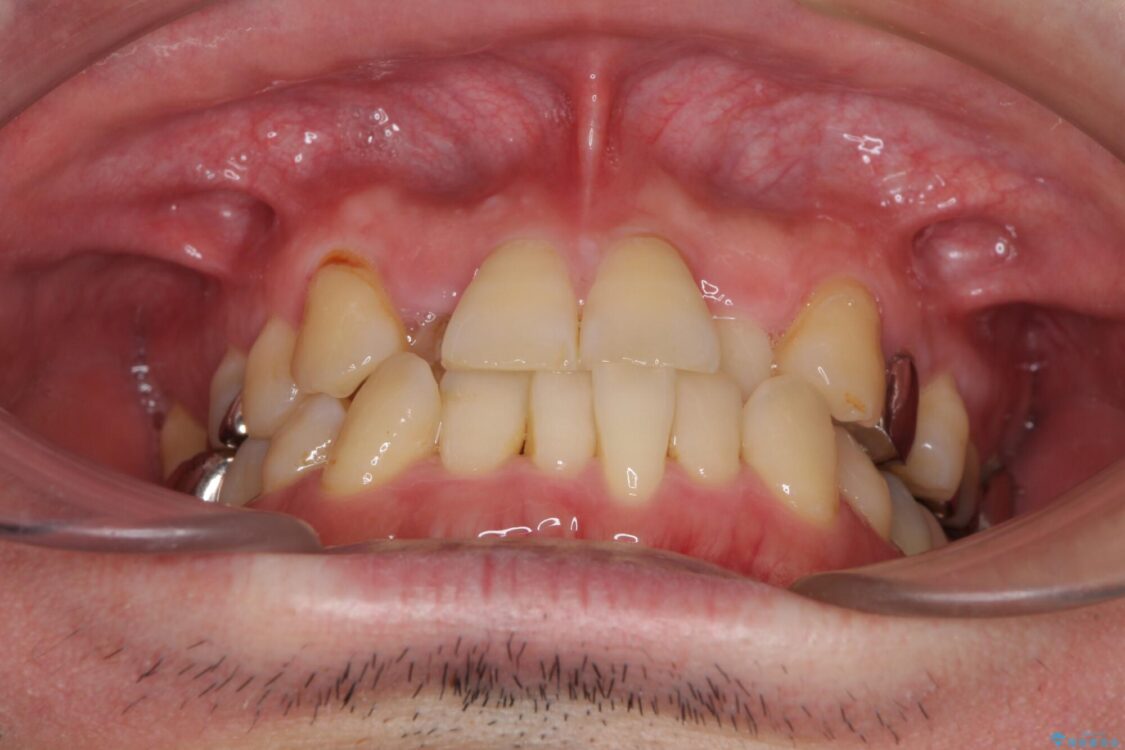

奥歯の痛みと前歯のデコボコを気にして来院された患者様です。

左右下顎の大臼歯は、ともに歯根が破折しており、抜歯が必要な状態でした。

放置したことで炎症による骨吸収が顕著であるため、骨造成を併用してインプラント埋入を行うこととしました。

咬み合わせは受け口傾向であり、上顎前歯の叢生が顕著であったことから、第1小臼歯抜歯による矯正治療も検討しましたが、下顎大臼歯を左右ともに抜歯するため、非抜歯による矯正治療を行うこととしました。

治療前

• 割れてしまった奥歯とデコボコの前歯 矯正治療とインプラント治療 治療前画像